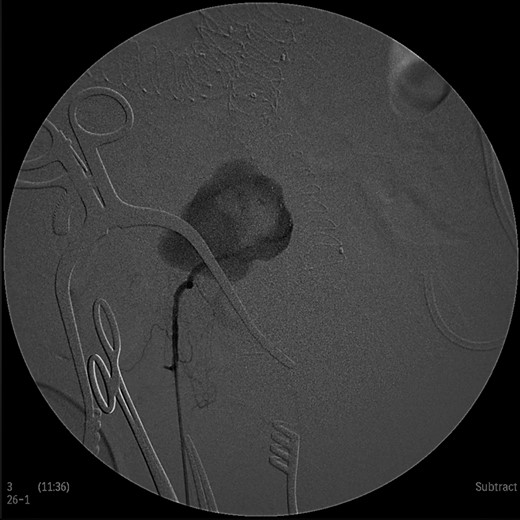

Under general anesthesia the patient was placed in prone position and a 15 cm transverse incision, slightly curvy was performed in the middle part of the right gluteal region between the posterior superior iliac spine and ischiac tuberosity. The gluteus maximus muscle was split and the inferior gluteal artery was identified as it entered the gluteal region through the greater schiatic foramen near the schiatic nerve below the piriformis muscle. The inferior gluteal artery was punctured using Seldinger technique and a 4Fr was introduced into the artery (Fig. 2). An angiography was made revealing the aneurysm of the right IIA and two feeding arteries, inferior gluteal artery and probably a branch of superior gluteal artery, filling the sac (Fig. 3). A 0.014 inch Pilot guide wire (Boston Scientific Corporation, USA) was inserted into the aneurysm and a microcatheter 3 Fr RENEGADE STC (Boston Scientific Corporation, USA) was advanced over the wire. After removing the wire, embolization microcoils (Interlock, Boston Scientific, USA) (two coils 22–600 mm, two coils 20–500 mm, three coils 18–500 mm) were introduced into the aneurysm sac (Fig. 4). A 5 Fr sheath was subsequently placed, a 5Fr RIM catheter (Cordis, USA) was advanced to the aneurysm sac through a 0.035 inch Terumo guide wire (Glidewire, Terumo Corporation, Japan) and selective catheterization of the second feeding artery was performed (Fig. 5). Embolization coils (Interlock, Boston Scientific, USA) were inserted into the two feeding arteries (two coils 15–400 mm) (Fig. 6). Completion angiogram depicted absence of blood flow into the aneurysm and the runoff vessels (Fig. 7). The patient had an uneventful recovery period without buttock claudication, ischemic complications and discharged in good condition. A follow-up CT aortography after 6 months depicted complete thrombosis of the aneurysm (Fig. 8).

Intraoperative angiogram showing the presence of the aneurysm and two collateral vessels, embolization with coils of the sac and two feeding arteries. Completion angiogram depicted absence of blood flow in the IIA aneurysm and the runoff arteries.